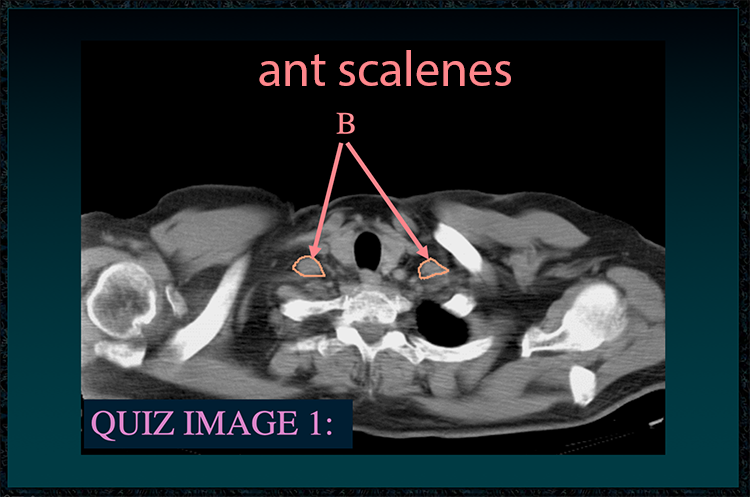

◂Chest Anatomy Review